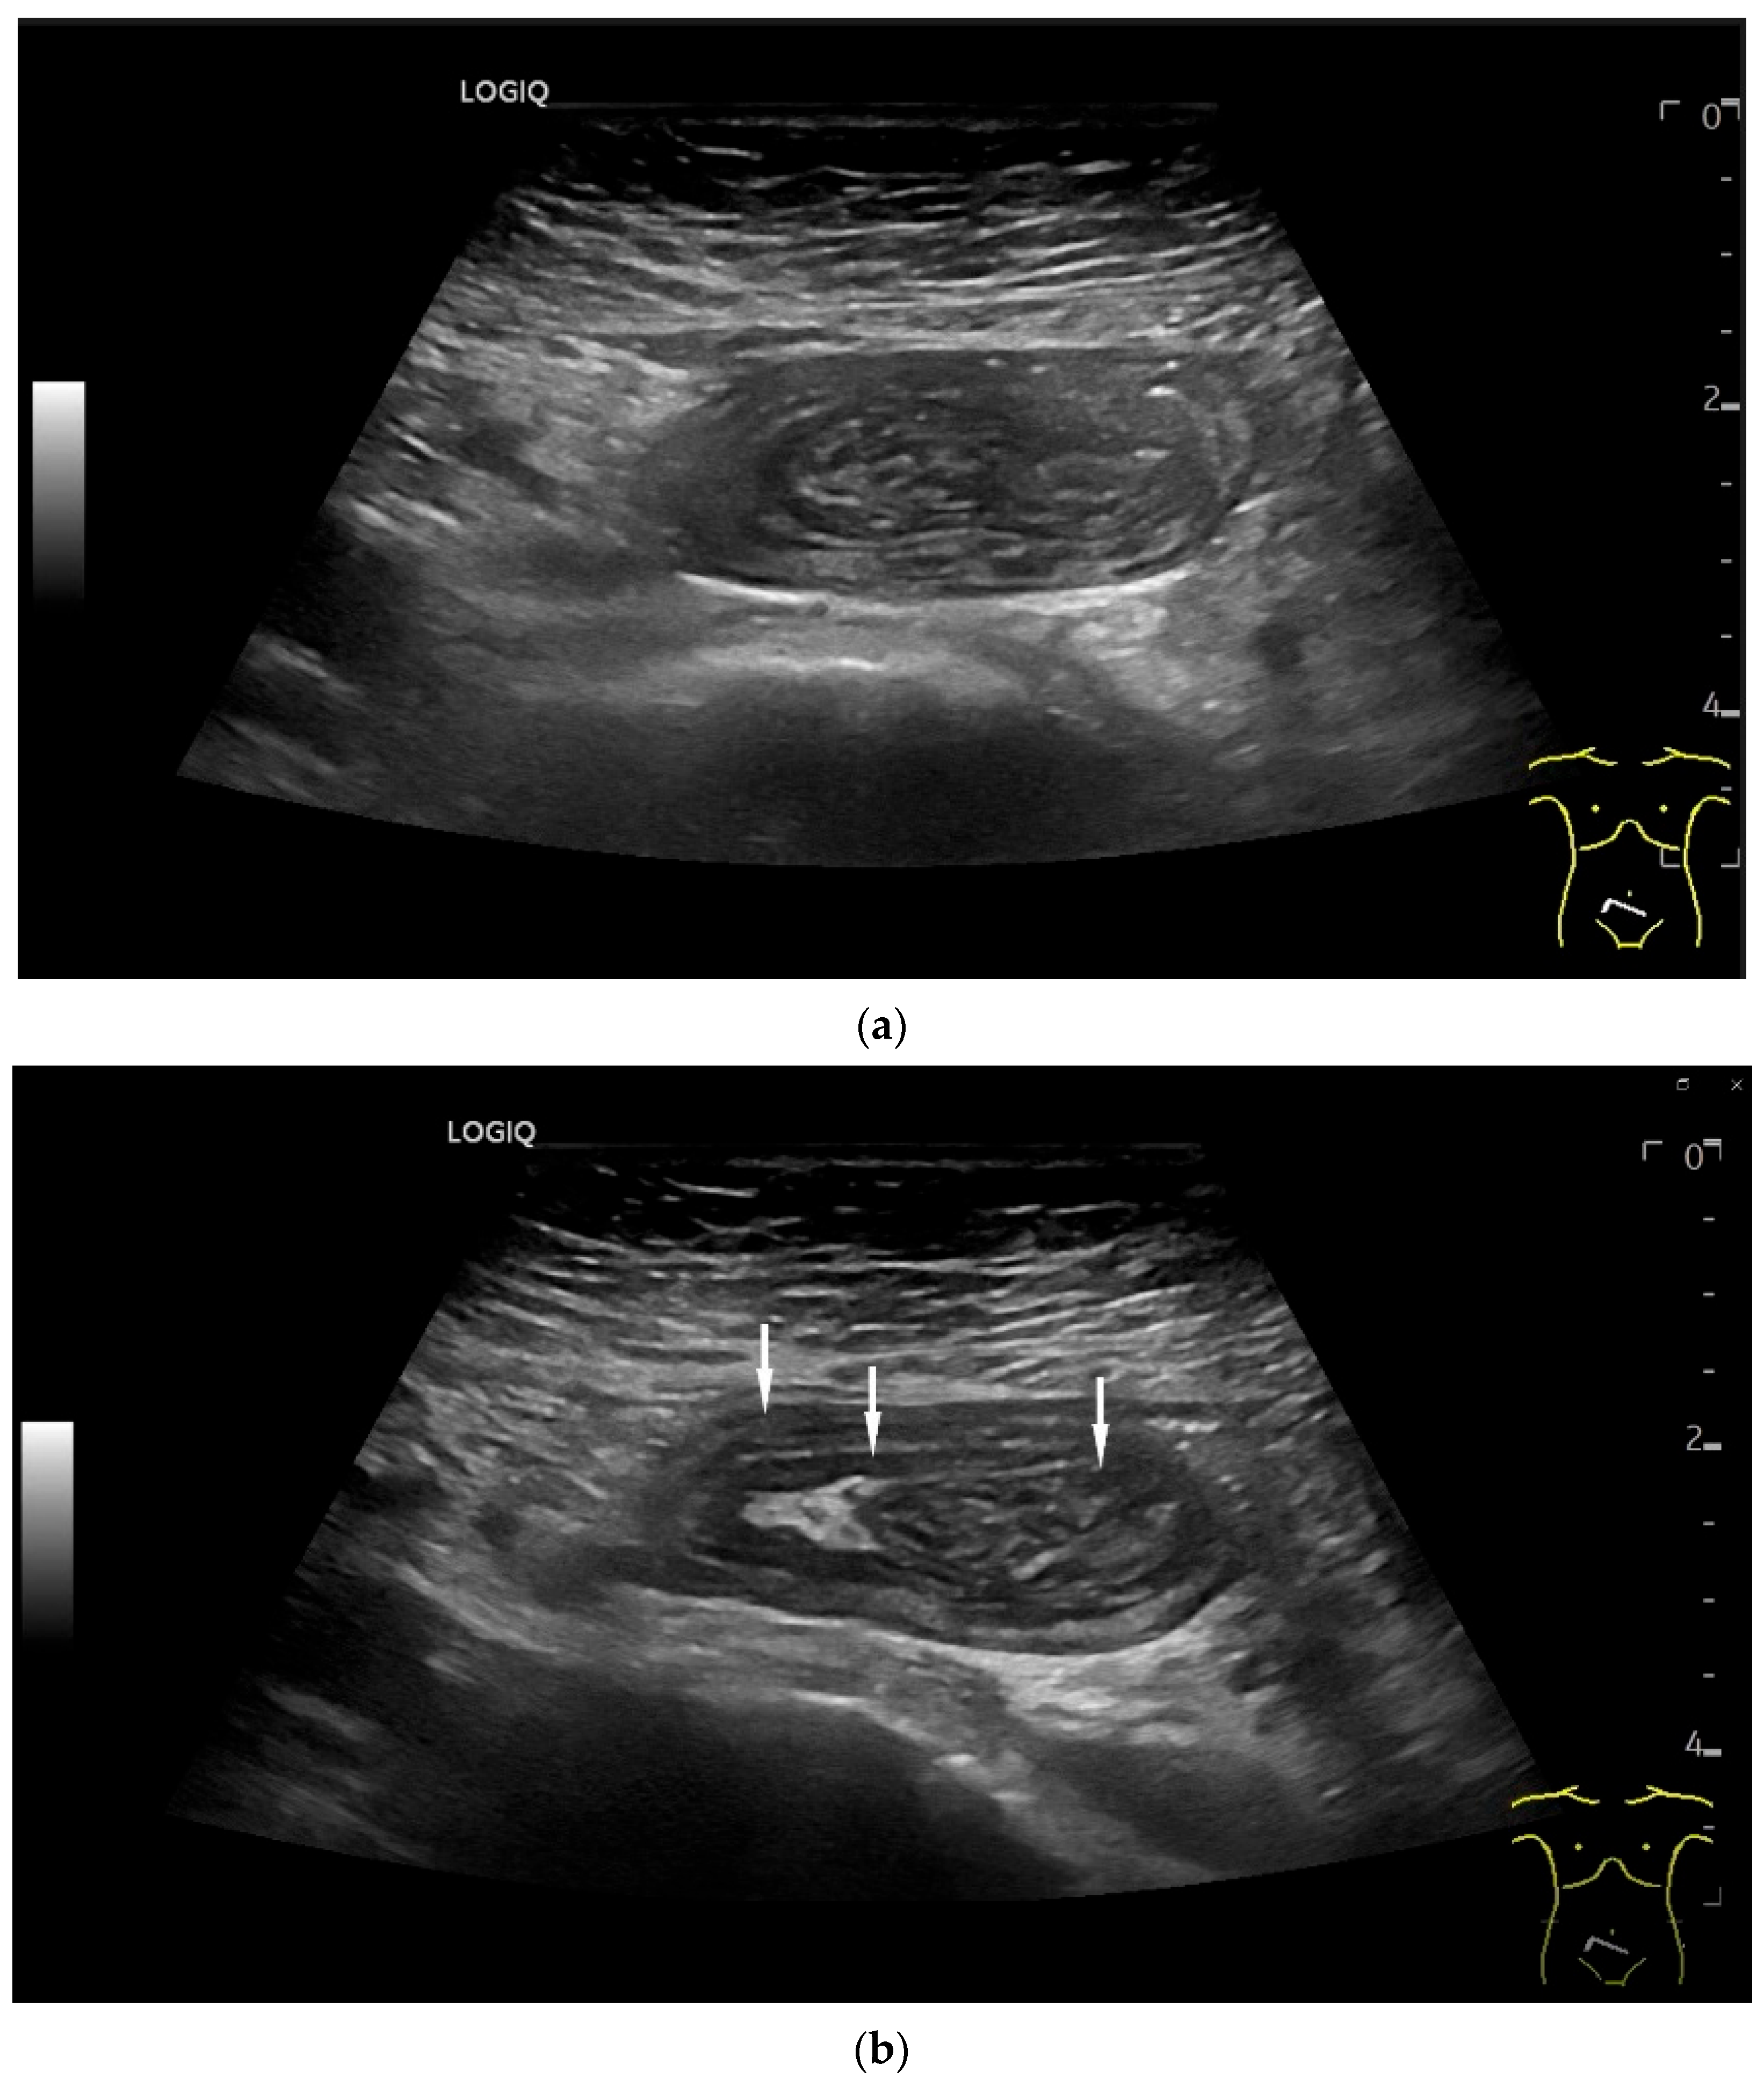

Figure 3.

Intussusception. In the ileum, the intestine is inverted. Instead of the usual five layers, there are many onion-skin-like layers (a). The intestine is folded in on itself several times. The wall is marked with arrows (b).

Figure 4.

NEN in the ileum: an approximately 14 mm hypoechoic nodular tumor is visible (a). Subsequently, peristalsis reveals a hypoechoic wall thickening (W) and hyperechoic luminal reflex (L) (b) and, finally, causes the tumor to be obscured by the luminal contents and dorsal artifacts (c). The region of the tumor is marked with a yellow arrow in all three images.